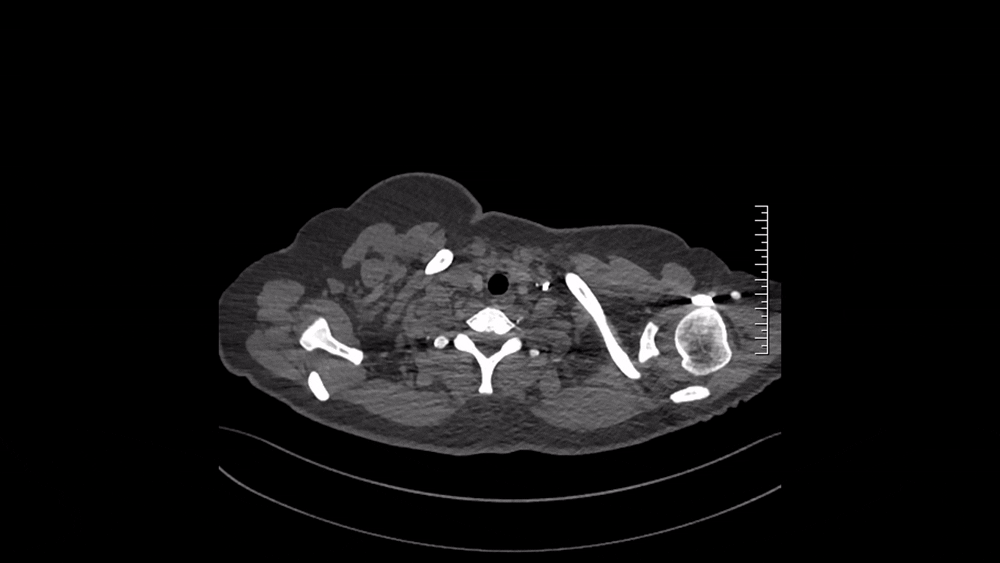

图4 2024.11.4 CTPA纵隔窗

仔细阅读CTPA:肺窗可见多发磨玻璃影,马赛克征象,这是肺血流灌注不均的表现(图3);纵隔窗可见肺动脉主干增粗,提示肺动脉压力升高;右肺上叶、中叶血管纹理稀疏,多个肺动脉亚段及分支(RA1、RA2、RA3、RA4、RA5、RA10、LA4、LA5为著)狭窄、闭塞病变,这些提示肺动脉慢性血栓表现(图4)。